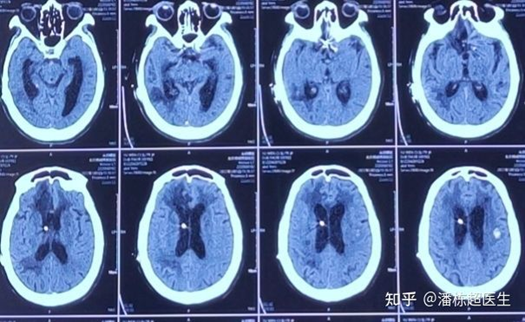

术后给与患者低压引流后,第二天就恢复了清醒!

其实整个诊断治疗过程中,最重要的一步是:判断是否需要取出分流泵,因为一旦取出后不改善,就没有办法挽回了。而我术前判断有必要取出分流泵的重要依据,就是判断她属于低压性脑积水(不是正常压力脑积水)。

效果:术后第二天患者清醒,遵嘱动作。